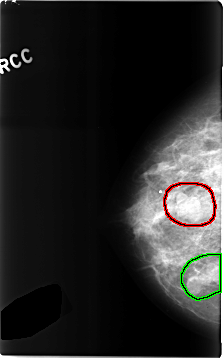

C_0306_1.RIGHT_CC

RIGHT_CC LINES 4648 PIXELS_PER_LINE 2912 BITS_PER_PIXEL 12 RESOLUTION 50 OVERLAY

FILE: C_0306_1.RIGHT_CC.OVERLAY

TOTAL_ABNORMALITIES 2

ABNORMALITY 1

LESION_TYPE MASS SHAPE LOBULATED MARGINS CIRCUMSCRIBED

ASSESSMENT 4

SUBTLETY 5

PATHOLOGY BENIGN

ABNORMALITY 2